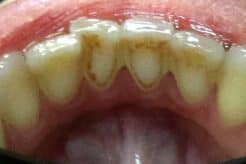

Tartar, also called dental calculus, is a yellow or brown colored deposit that forms when plaque hardens on your teeth and contributes to their decay.

Plaque is riddled with harmful bacteria that damage tooth enamel and cause cavities. If you don’t remove the plaque from your teeth, it hardens into tartar. Tartar consists mostly of mineralized dead bacteria and proteins.

Not only does tartar damage the teeth and gums, it also poses a cosmetic problem. Because tartar is more porous, it absorbs stains easily. If you drink coffee or tea, or if you smoke, it is especially important to know how to remove tartar from your teeth without going to a dentist, and how to prevent it from forming again.